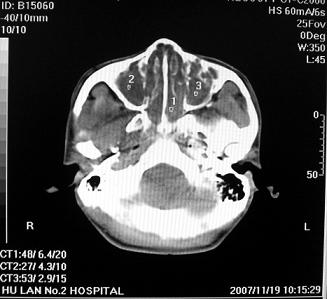

软组织密度影填满上颌蚪 筛窦及鼻腔,并导致筛骨 上颌窦内侧壁明显骨质破坏。多考虑:内翻性乳头状瘤!

双侧鼻腔内低密度软组织影,骨壁无明显破坏,鼻腔无扩大,双侧上颌窦、筛窦软组织影,窦壁增厚,结合临床考虑鼻息肉合并慢性上颌窦炎。

考虑鼻腔内翻性乳头状瘤,筛窦、上颌窦炎症。建议进一步检查。